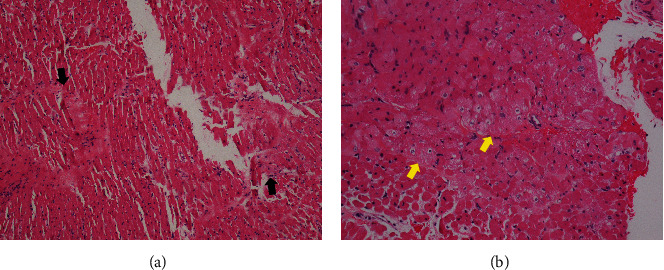

虽然活动性感染通常是心脏移植手术前的禁忌症,但一名被诊断为扩张型心肌病的 16 岁男子在脓毒性休克和心源性休克的情况下,仍患有活动性可能侵袭性肺曲霉菌病和细菌性肺炎,并成功接受了心脏移植手术。

Although active infection is generally a contraindication before an orthotopic heart transplant, a 16-year-old man diagnosed with dilated cardiomyopathy successfully underwent an orthotopic heart transplant despite having active probable invasive pulmonary aspergillosis and bacterial pneumonia in the presence of septic and cardiogenic shock.